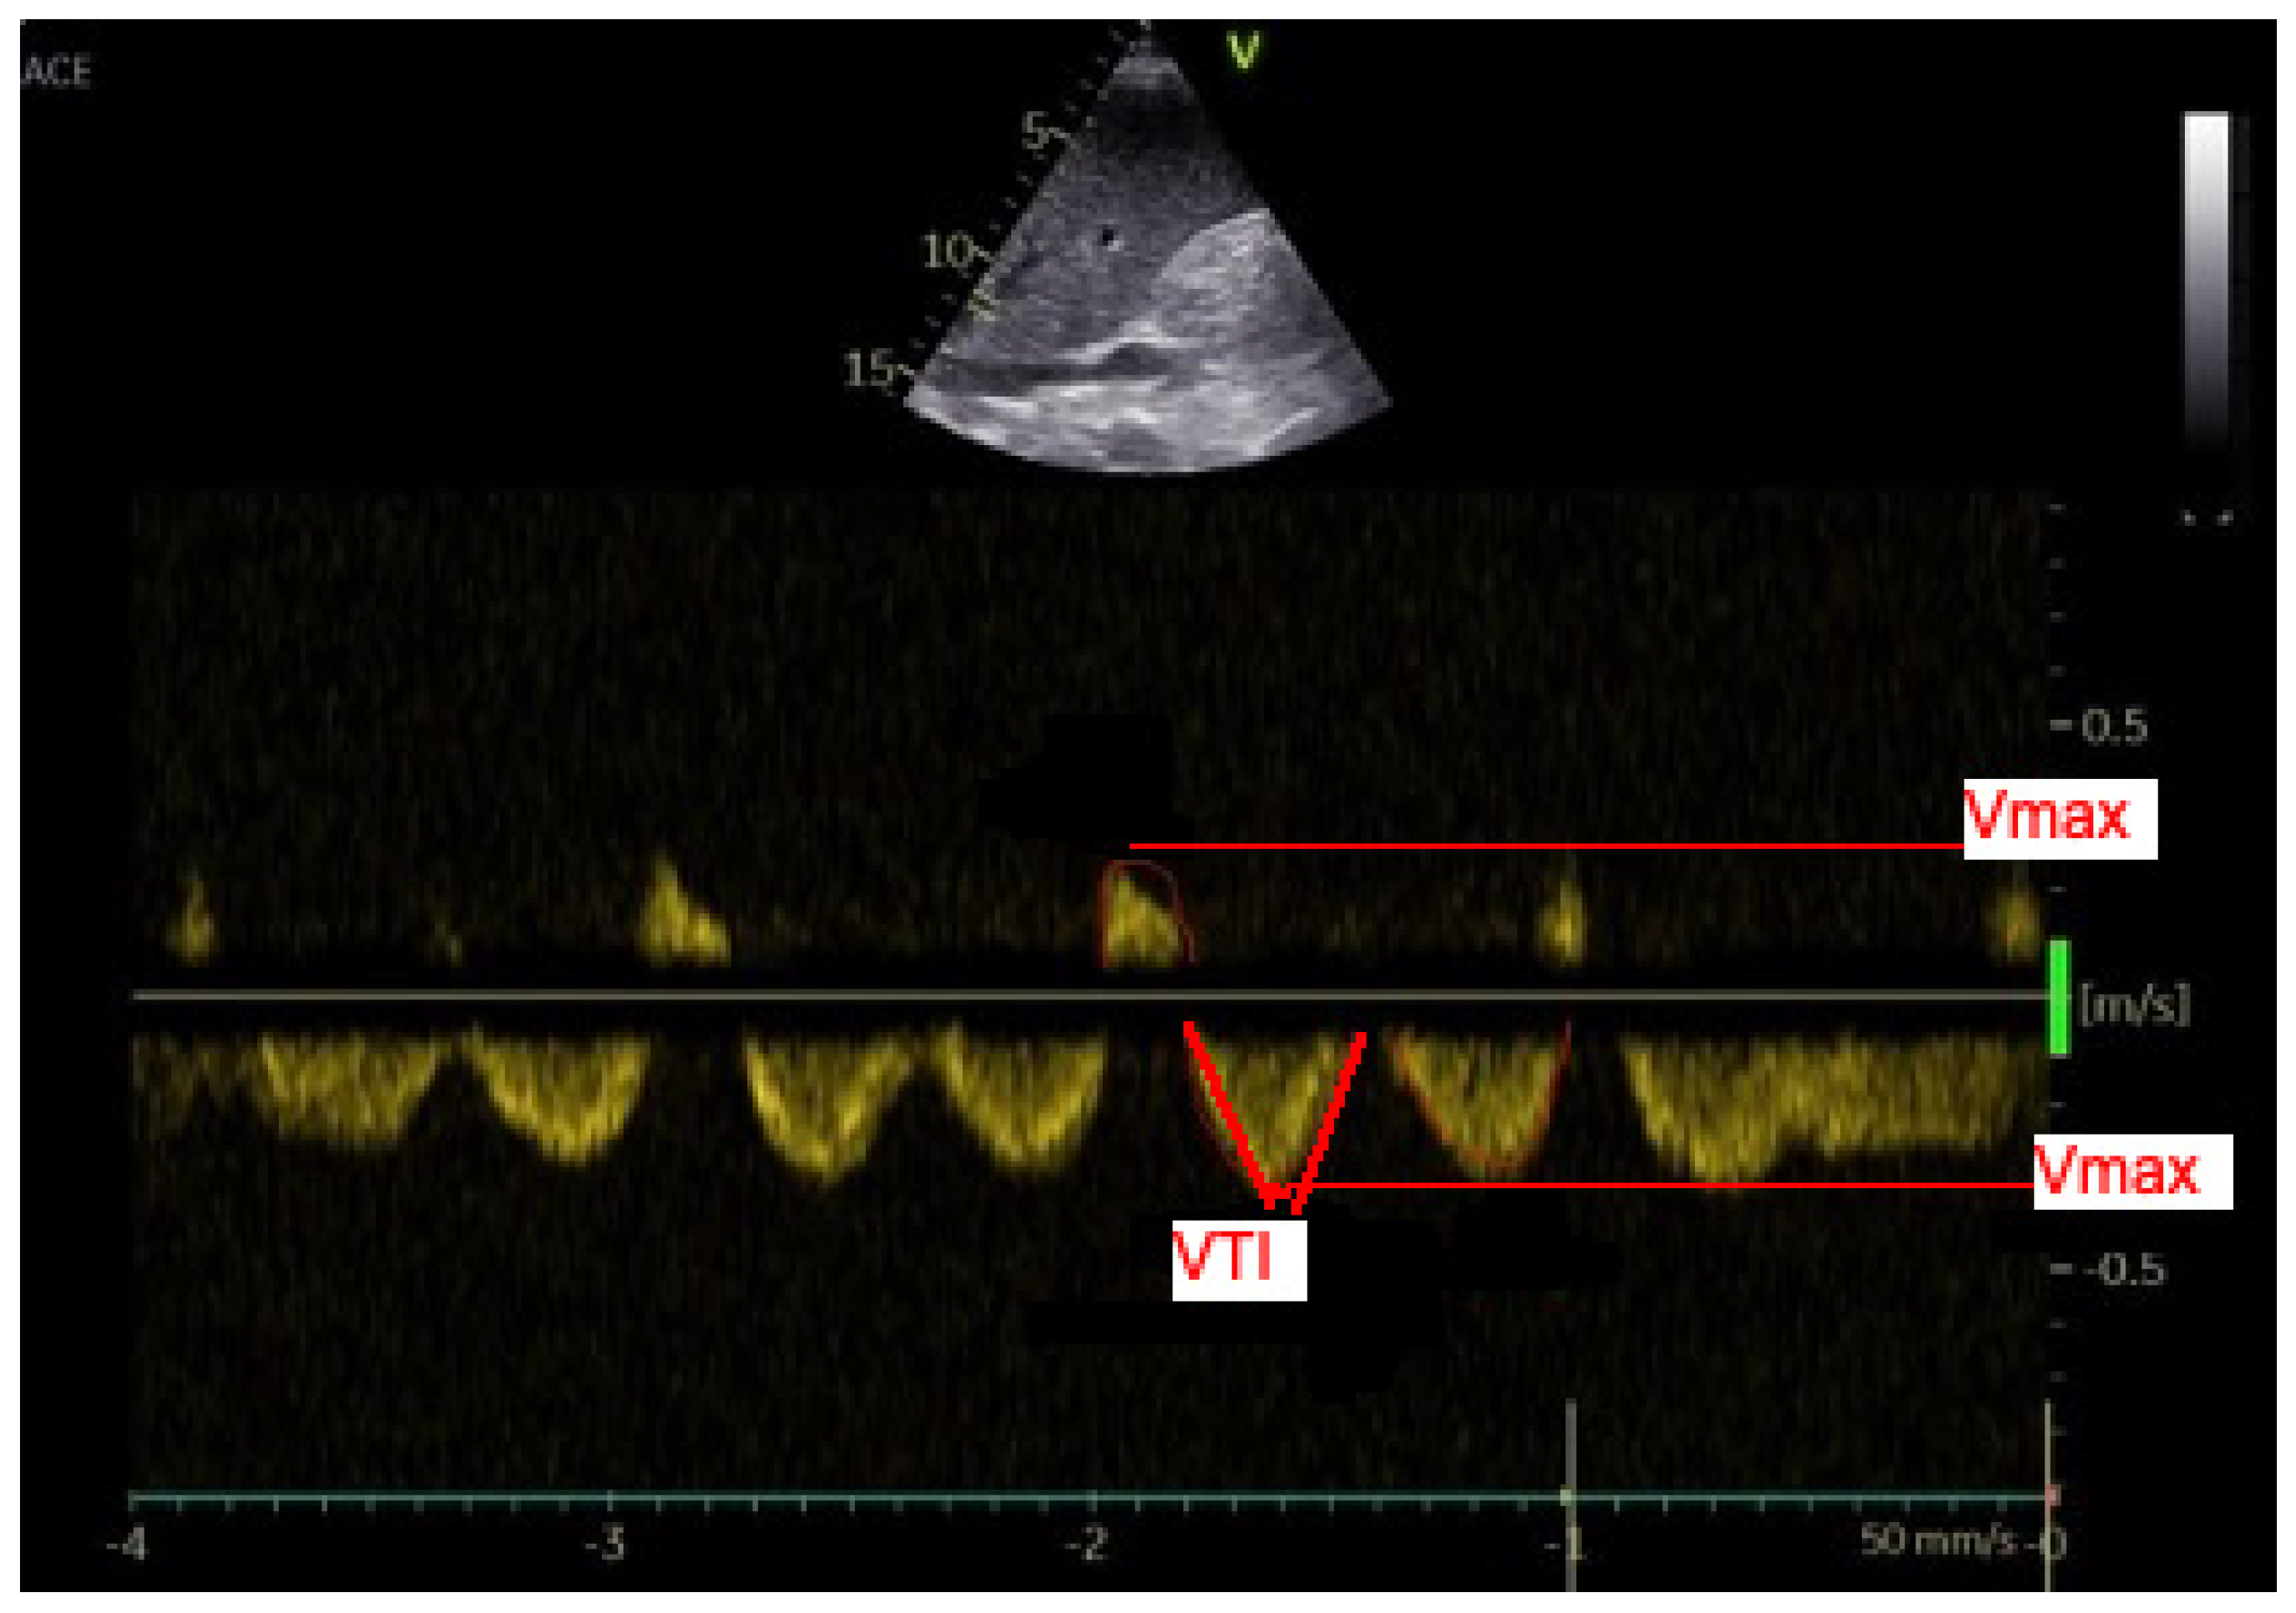

2.3. Analyses of the Hepatic Veins

Figure 2. Doppler US analysis of the hepatic veins–maximum velocity and velocity-time integral were measured (a line was adjusted to the maximum point and continuous wave Doppler’s spectral curve was calculated by the machine. A and V waves are retrograde, S and D are anterograde waves).